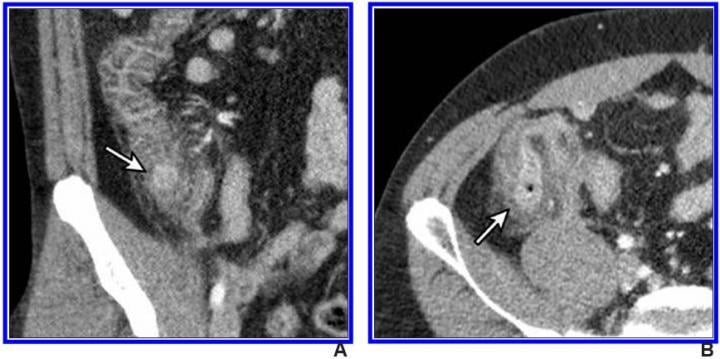

IV contrast-enhanced 2-mSv 4-mm-thick transverse and coronal (b) CT images show inflamed diverticula (arrows), segmental colonic wall thickening, and adjacent pericolic fat stranding. Image courtesy of the American Roentgen Ray Society (ARRS), American Journal of Roentgenology (AJR)

April 9, 2021 — According to an open-access article in ARRS' American Journal of Roentgenology (AJR), IV contrast-enhanced 2-millisievert CT (2-mSv CT) is comparable to conventional-dose CT (CDCT) for the diagnosis of right colonic diverticulitis.

"By mitigating concern of missed diagnosis of right colonic diverticulitis, our results further support the use of low-dose CT for suspected appendicitis," wrote first author Hae Young Kim from the department of radiology at Korea's Seoul National University Bundang Hospital. "To our knowledge," Kim et al. maintained, "this is the first study to formally measure the diagnostic performance of CT for right colonic diverticulitis."